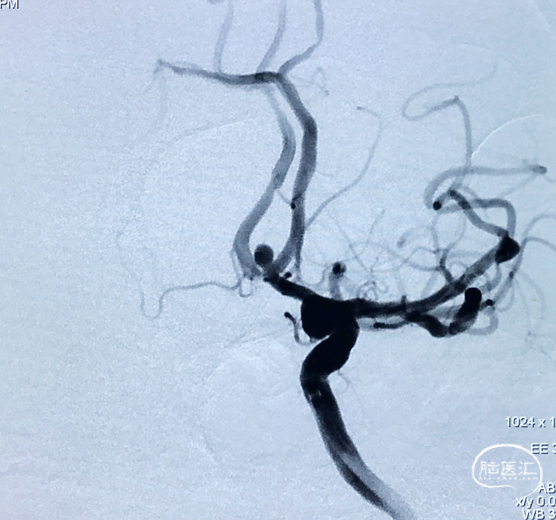

动脉瘤形态如下图,为前交通相对宽颈动脉瘤:

根据造影结果诊断为前交通动脉瘤

观察动脉瘤位于前交通动脉,形态较规则,相对宽颈,测量得直径约3.3mm,计划通过球囊辅助弹簧圈栓塞方式对动脉瘤进行致密栓塞

术前造影

术前工作位造影